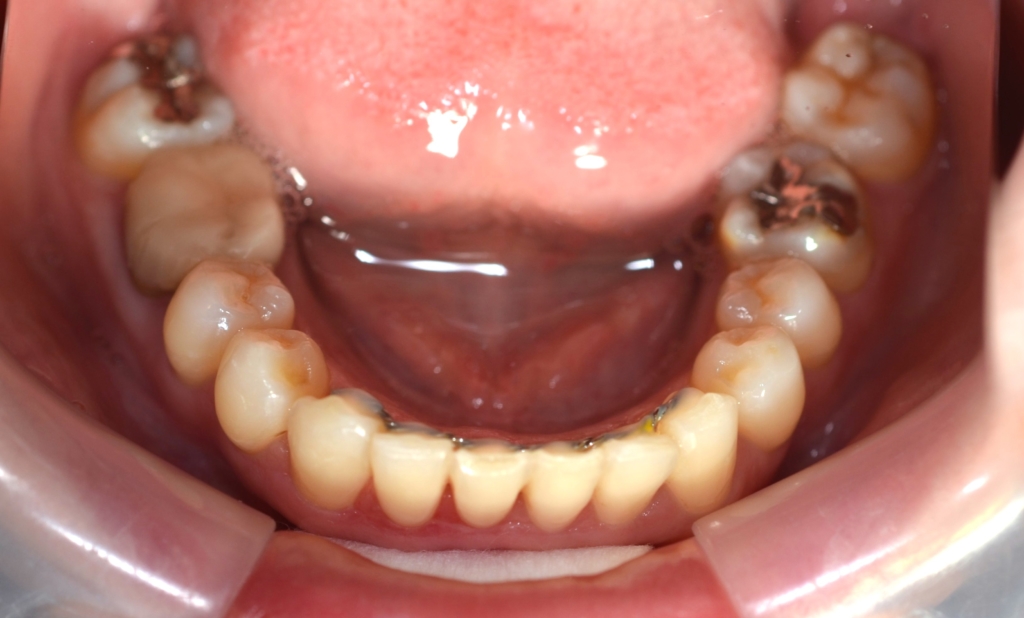

【経過】

上の前歯が並んだので、ガミースマイルを改善させるために、前歯部にアンカースクリューを植立して準備を整えます。

そうこうしているうちに、下の歯列も並んで整ったので、

「上の前歯の圧下」と「下の前歯の後方への移動」を同時進行で行うことにしました。

そこからワイヤーを伸ばすことで「圧下」の力を加えることが出来るようにしました

ガミースマイルの改善が済んだ後、あらためて上の前歯を引っ込めるステップに入りました。